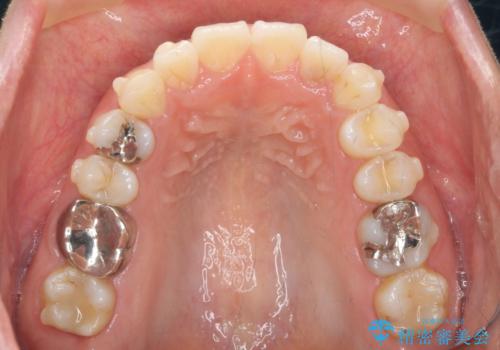

前歯の角度を改善するマウスピース矯正

- インビザライン

- 2年

しっかりと拡大を行い、IPRも併用したことで歯並びと前歯の角度を大幅に改善することができました。